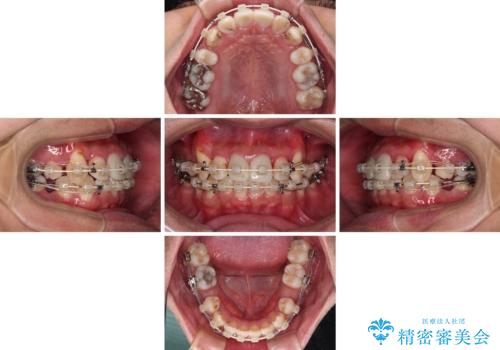

- 矯正装置

- 審美装置

- 治療期間

- 2年6ヶ月

前歯の歯列が整ったことで、歯磨きが大変やりやすくなり、患者様には大変満足していただけました。